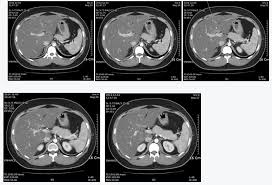

복부 CT(Computed Tomography, 컴퓨터 단층 촬영)은 복부 내의 구조와 장기를 상세히 살펴볼 수 있는 중요한 진단 도구입니다. 다양한 복부 질환을 조기에 발견하고 정확한 진단을 내리는 데 도움을 줄 수 있으며, 이는 치료 방향을 결정하는 데 중요한 역할을 합니다.

- 간종양: 간암이나 양성 간종양(예: 간혈관종, 간세포종 등)을 진단하는 데 복부 CT는 중요한 역할을 합니다. CT 이미지는 종양의 크기와 위치, 주변 조직과의 관계를 파악하는 데 도움을 줍니다.

복부 CT는 복부 내의 다양한 질환을 정확하게 진단하는 데 필수적인 도구입니다. 간, 췌장, 신장, 장, 혈관 및 외상 등 다양한 복부 질환을 평가하고 조기에 발견하는 데 도움을 주며, 이를 통해 적절한 치료 계획을 세울 수 있습니다. 정확한 진단과 조기 치료는 건강 회복에 중요한 영향을 미치므로, 복부 CT 검사를 통해 정확한 진단을 받는 것이 중요합니다.